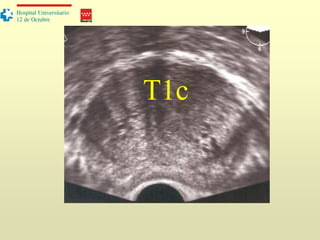

T1c

Estadificación

T2: tumor localizado dentro de la próstata

T3a: Tumor que afecta la cápsula

T3b: Invasión de vesículas seminales

T4: invasión de órganos adyacentes (recto, vejiga…)